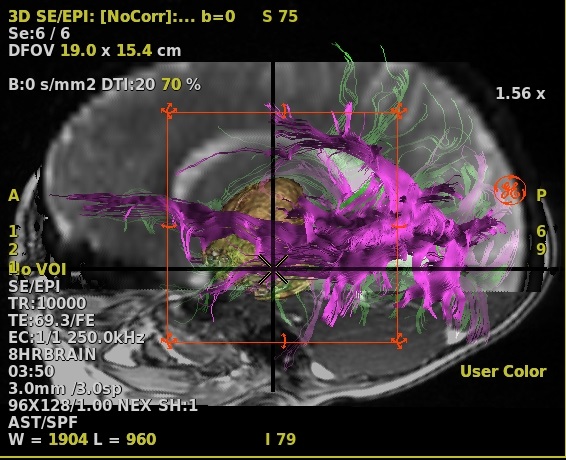

- To merge the 4 views (FiberTrak, Sagittal, Coronal and Axial), follow these steps.

- From one of the 3D viewport plane selection menus, click Axial.

- Scroll through the images to locate an image that displays the pathology of interest

- With the mouse in

, click an image and drag it over the FiberTrak viewport and drop it in the "Drop here to merge the views" box.- Respond to any prompts

Figure 7. 4 views merged

- Respond to any prompts